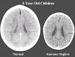

La foto que podemos ver arriba es de los cerebros de dos niños de tres años, ¿cuál es la diferencia entre estos dos cerebros? El amor de la madre. El cerebro de la izquierda es de un niño que ha sido amado y cuya madre ha cubierto todas sus necesidades emocionales, mientras que el de la derecha es de un niño que ha sido ignorado y cuyas necesidades no han sido atendidas.

Además de que el cerebro de la izquierda es más grande que el de la derecha, éste carece de algunas áreas fundamentales presentes en la imagen a la izquierda, lo cual hará que el niño desarrolle menos capacidades, sea menos capaz de empatizar con los demás, y más propenso a las adicciones, a la violencia y a desarrollar serios problemas mentales y de salud.

La diferencia de tamaño entre estos dos cerebros es lo suficientemente elocuente como para plantearse la crianza que se le dará a un hijo.